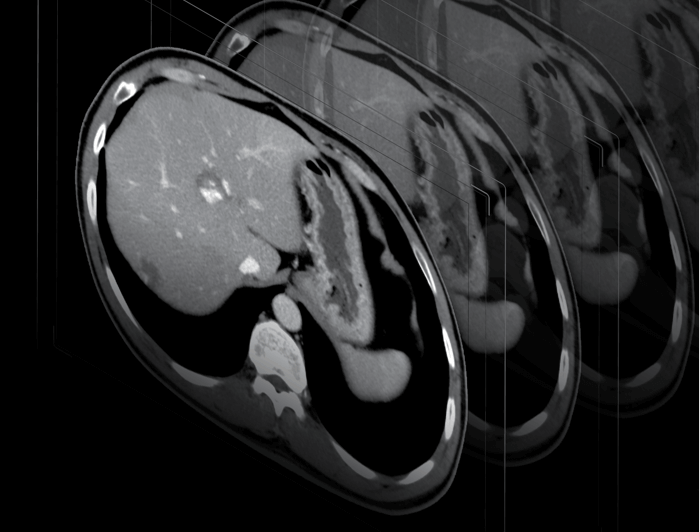

精准图像重建,清晰显示微小病灶

0.5mm薄层扫描结合百万矩阵

精准图像重建

1024X1024高清重建矩阵

提高X-Y平面空间分辨率,内耳、小关节、肺部等微小细节纤毫毕现

0.5mm层厚

突破0.5mm层厚的精细图像,精微显示细小结构